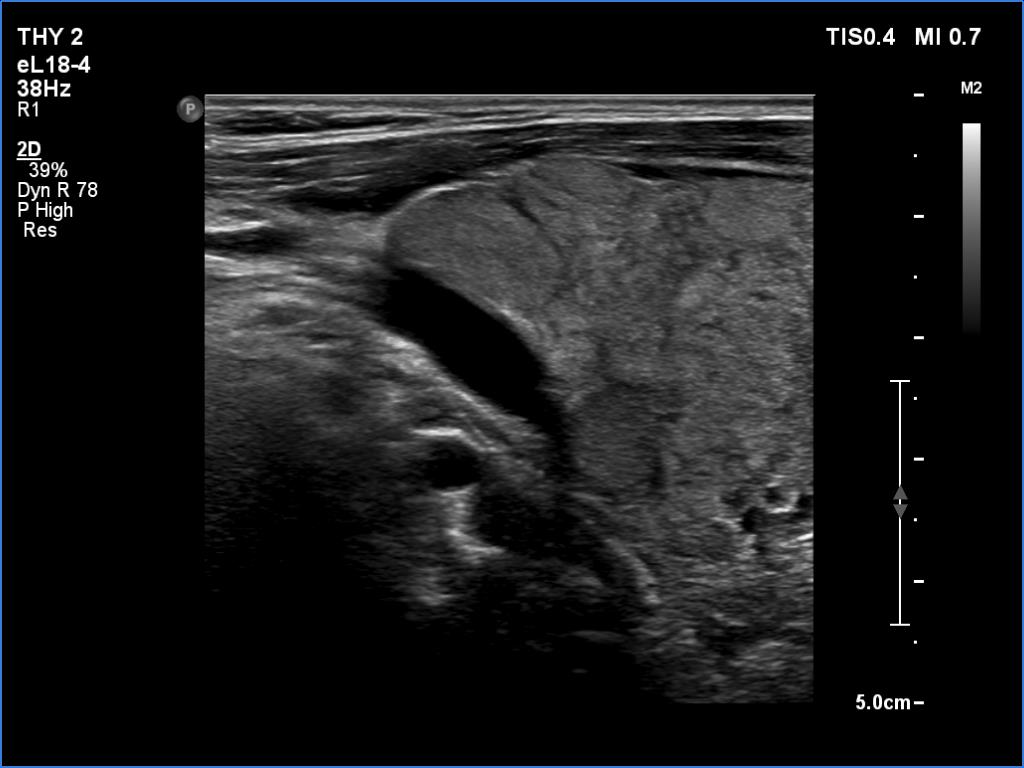

Lymphocytic thyroiditis - case 609

Follow-up investigation 6 years after the first visit (ultrasonographic picture 2)

Right lobe, longitudinal scan

Upper part of the right lobe, longitudinal scan.